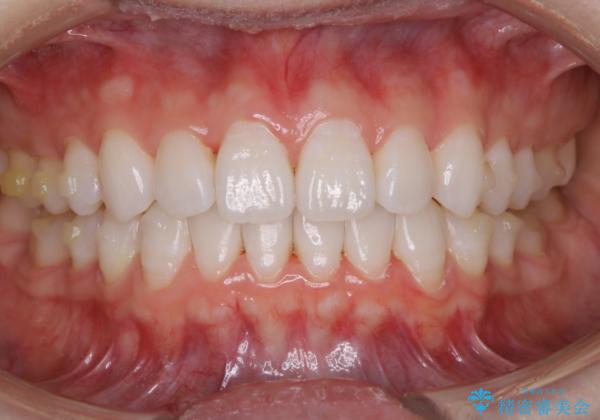

インビザラインで矯正治療中に、クリーニングを行ったbeforeafter写真です。

自費クリーニング(pmtc)30分コース¥5000+tax

矯正治療中は、虫歯や歯周病のリスクが高くなったり、長い時間マウスピースを着用することにより、ステイン(着色)がしやすくなることがあります。

そのため矯正治療中は、(マウスピース矯正・ワイヤー矯正共に)クリーニングを行い、こまめに汚れを取り除き、お口のケアをすることが大切です。